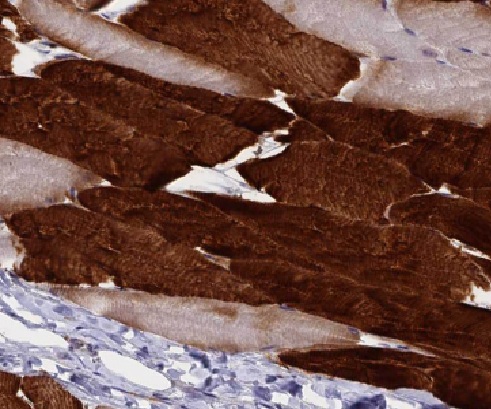

| 验证图片 | Immunohistochemistry of paraffin-embedded human skeletal muscle slide using FNab04773(LIFR Antibody) at dilution of 1:50 human skeletal muscle tissue were subjected to SDS PAGE followed by western blot with FNab04773(LIFR antibody) at dilution of 1:800 |